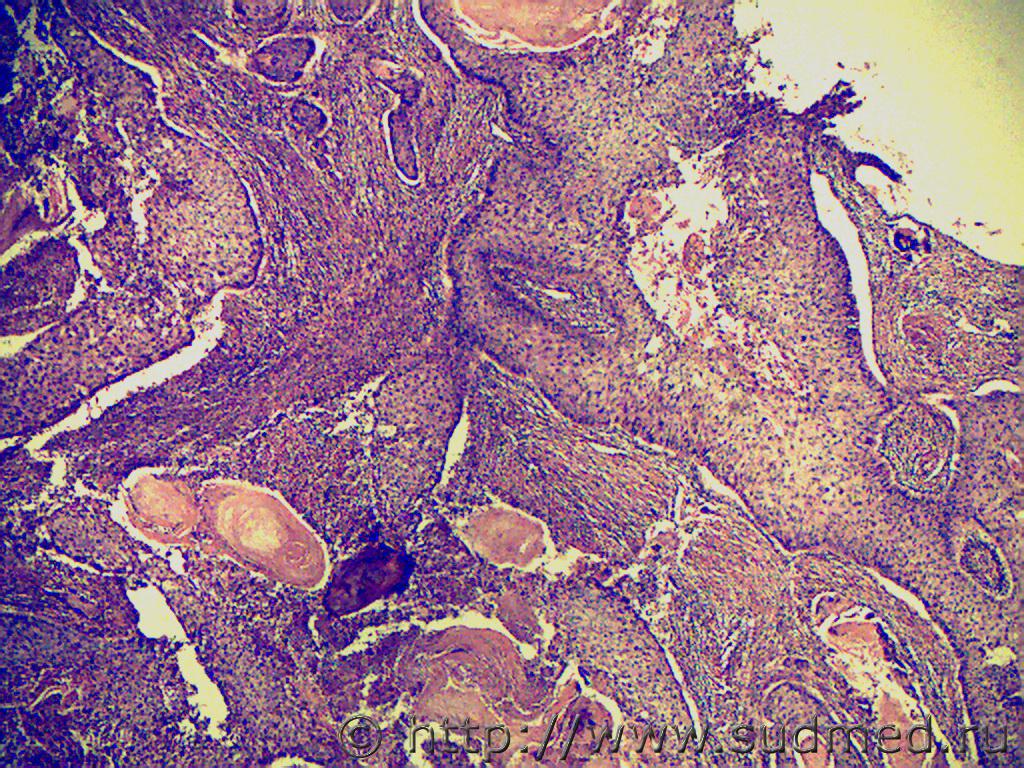

jaklin Плоскоклеточный рак, т.к. есть жемчужины. 20.11.2013 - 19:17

Медик жемчужины.

Это неспецифический признак.

В псевдок... 20.11.2013 - 19:26

jaklin Это неспецифический признак.

В псевдокарциноматозн... 20.11.2013 - 22:26

Медик Если присмотреться внимательно, можно рассмотреть ... 20.11.2013 - 19:34

Морфолог Если присмотреться внимательно, можно рассмотреть ... 24.03.2014 - 12:03